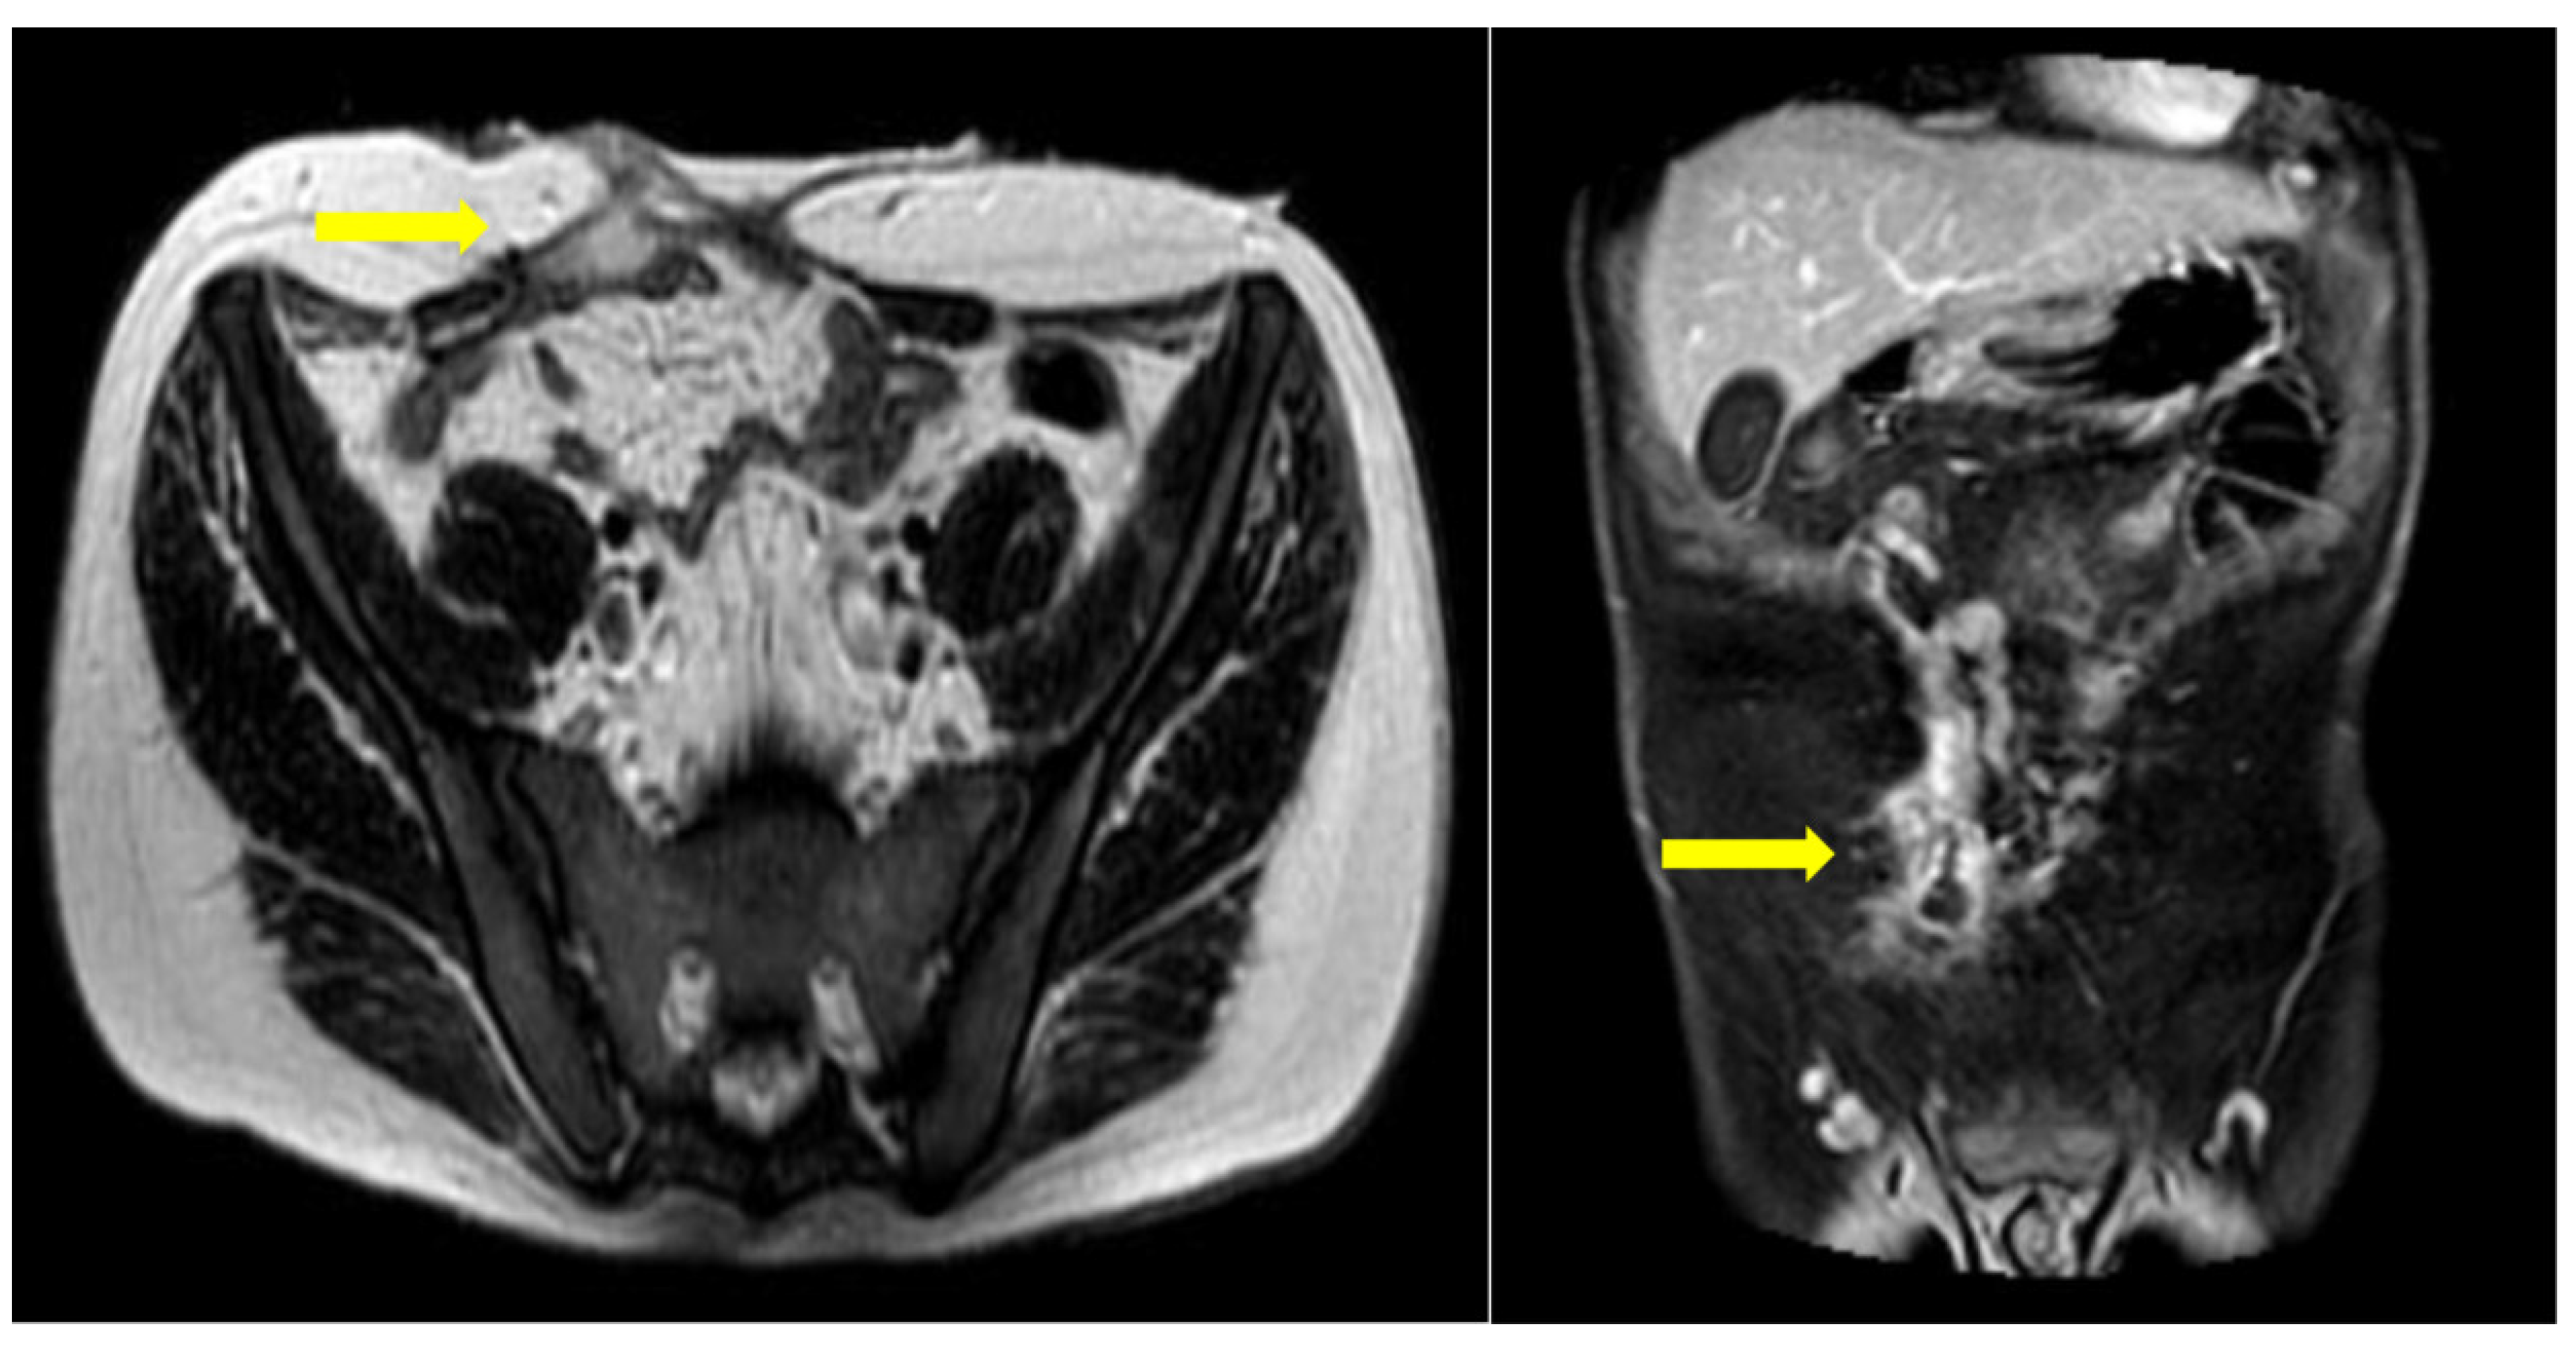

Six months postoperatively, the patient was referred to our department for further diagnostic management and treatment of the remaining enterocutaneous fistula (Figure 2). A variety of diagnostic tests (hematological, endocrinological, gastrointestinal) and multiple imaging examinations were performed. There were no abnormal findings, except for vitamin Κ deficiency, as expected in the context of chronic non-intestinal feeding. The Magnetic Resonance Imaging (MRI) enterography confirmed the presence of a fistula between the jejunum and the skin, with the internal stoma of the fistula at a distance of about 65–70 cm from the Treitz (Figure 3). Therefore, given that the patient has a functional bowel slightly more than half a meter in length, the diagnosis of short bowel syndrome with the accompanying problems of malnutrition was established.

Figure 3.

MRI enterography for follow-up. A gap in the anterior abdominal wall is seen, following open surgery with enterectomy. A peripherally enhancing fluid collection is seen juxtapositioned to the rectus abdominis muscle, in close connection with a collapsed ileal loop. This appearance is in keeping with a fistulous tract between adjacent bowel loops and the anterior wall.